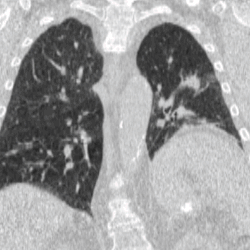

Four-dimensional computed tomography (4DCT) is a type of CT scanning which records multiple images over time. It allows playback of the scan as a video, so that physiological processes can be observed and internal movement can be tracked. The name is derived from the addition of time (as the fourth dimension) to traditional 3D computed tomography. Alternatively, the phase of a particular process, such as respiration, may be considered the fourth dimension.[1]

4DCT is used in radiation therapy planning to reduce doses to healthy organs such as the heart or lungs. Most radiation therapy is planned using the results of a 3D CT scan. A 3D scan largely presents a snapshot of the body at a particular point in time, however due to the time of the acquisition, in which the patient is likely to have moved in some way (even if only breathing), there will be an element of blurring or averaging in the 3D scan.[6] When it comes to treatment planning, this motion can mean there is less accuracy in the positioning of treatment beams, and reduce the likelihood of a repeatable set-up on the linear accelerator when it comes to treatment.[7]

To minimise physical movements of the patient, some sort of immobilisation is typically used. To overcome physiological motion, such as breathing, 4DCT acquires images at a range of times and positions, allowing the extent of motion to be visualised (e.g. from maximum inspiration to maximum exhalation). The treatment plan can then be designed with a knowledge of the full range of possible positions of important organs, and the tumour (target) itself.[8]

4DCT will usually involve a gating technique, such as breathing tracking, so that image acquisition is automatically triggered at set points.[9] This gating can also be applied at treatment, where the radiotherapy beam is only switched on at certain points in the breathing cycle (as in the deep inspiration breath-hold technique).[10]